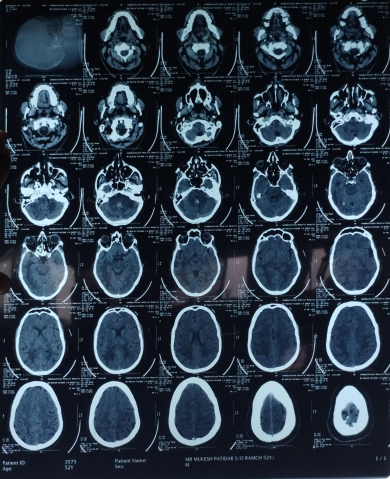

The patient’s routine blood investigations were normal. Serology for HIV, hepatitis B, C, and syphilis was negative. His MRI brain showed a parenchymal bleed in right temporo occipital regions with intra-ventricular leakage of blood and tiny petechial haemorrhage in brain parenchyma bilateral. extensive signal changes in cerebellar hemisphere, bilateral gangliothalamocapsular region, pons, midbrain and deep white matter of both cerebral hemisphere? Microangiopathy? CADASIL.

Early-onset dementia (onset before age 65) is a thought-provoking ailment with many possible causes, including early-onset familial Alzheimer’s disease, frontotemporal lobar degeneration, Parkinson’s dementia, Lewy body dementia, disorders of amino acid and organic acid metabolism, leukodystrophies, lysosomal storage diseases, disorders of metal metabolism, and mitochondrial diseases [6]. In our patient, the history, physical examination, laboratory investigations, and neuroimaging were not suggestive of these causes and prompted the search for a rare etiology. The most common MRI finding associated with CADASIL is basal ganglia and white matter hyperintensities in T2-weighted sequences that start as punctate or nodular foci and then often become confluent, extensive, and usually symmetrical, mainly in the periventricular region, anterior temporal pole, external capsule, the centrum semiovale, and frontal and parietal areas. In our patient, diagnosis was made mainly from MRI findings as seen in fig. 1, 2.

Fig. 1: Tiny petechial hemorrhages are seen in bilateral basal ganglia, white matter of both cerebral hemisphere, midbrain, pns and cerebellum. Diffuse cerebral and cerebellar atrophy is seen with enlarged ventricle due to atrophy. Acute to subacute parenchymal bleed is seen in righttemporo–occipital region. minimal intraventricular leakage of blood is also seen in 4th ventricle